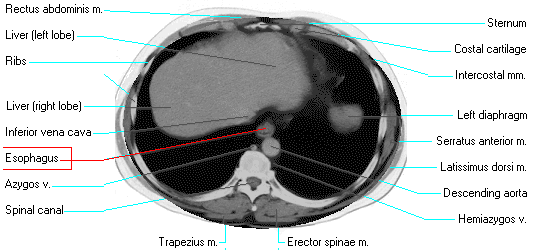

The oldest test was a barium swallow or upper GI exam. Also useful is a CT scan (CT #2) , and normal CT#3, and CT#4, through the chest and cross sectional anatomy here and here.